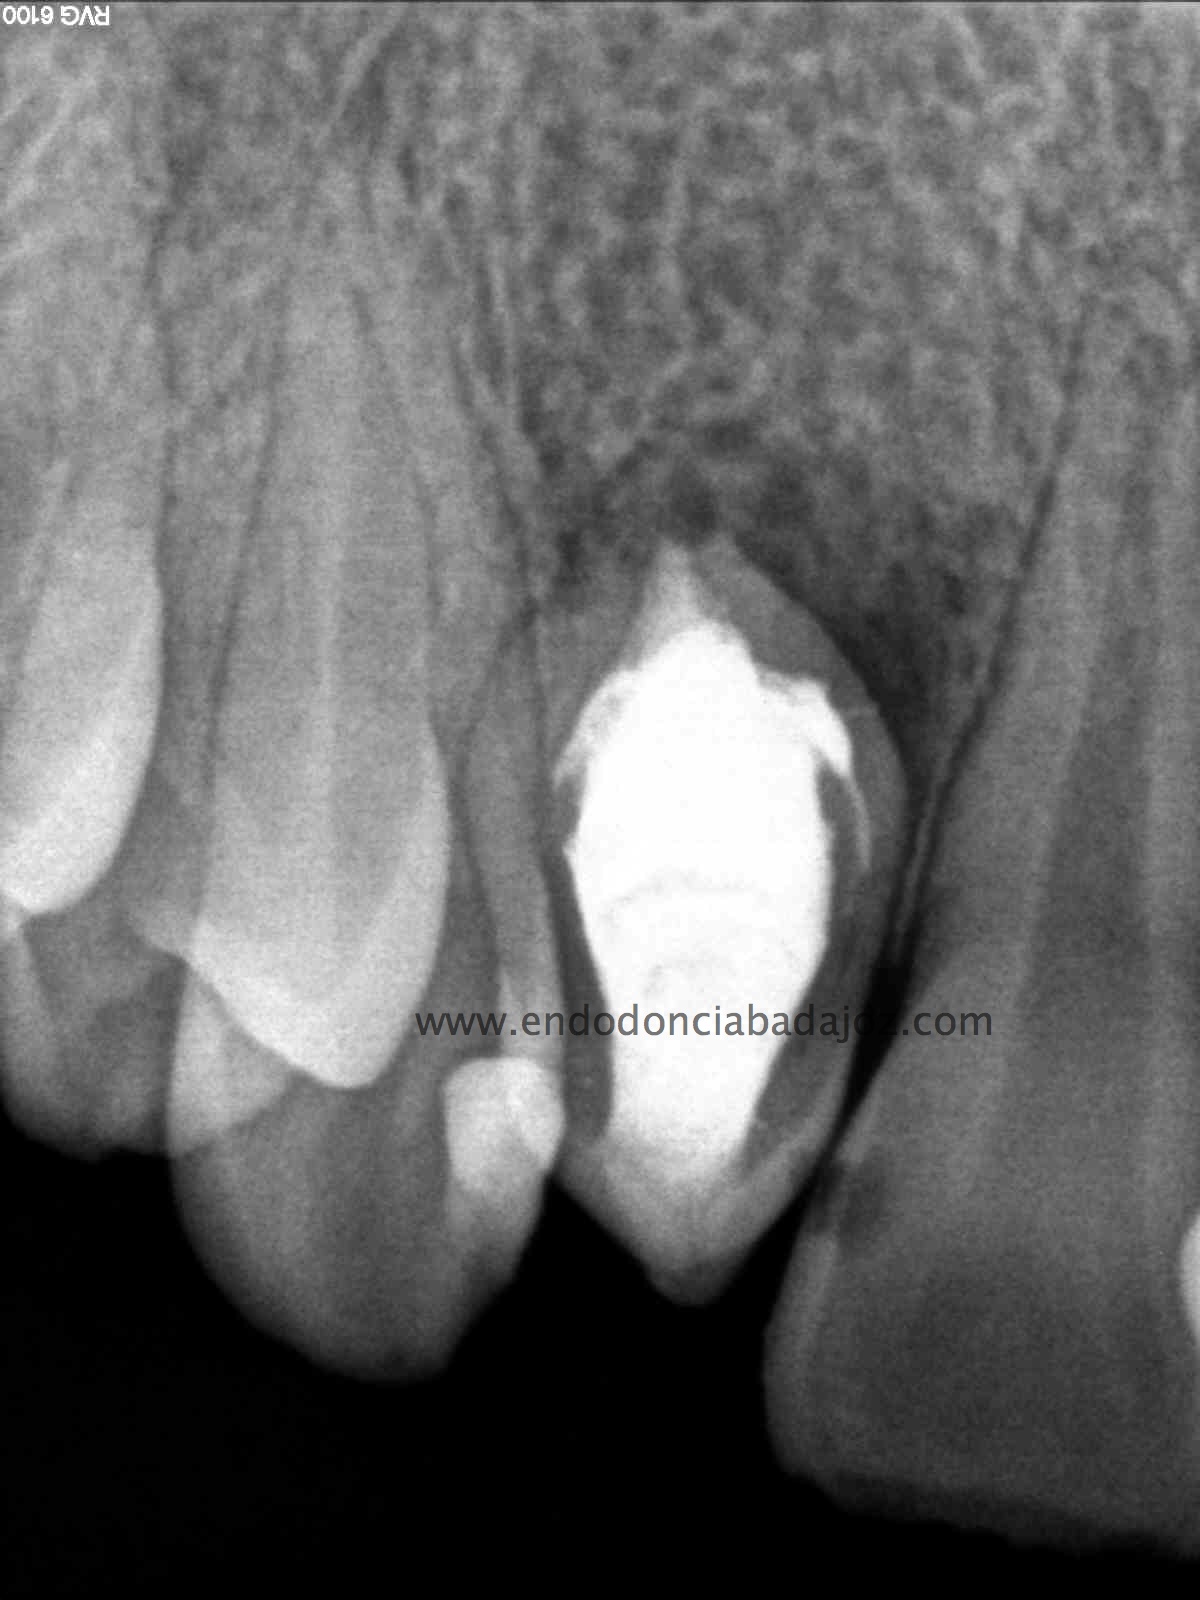

Se planteó el caso con una apertura del mismo y tratamiento de todo el conducto con puntas de ultrasonido desbridando las paredes e intentando no eliminar demasiado tejido dentinario. El primer paso sería conseguir una permeabilización del conducto:

Como defensor del H de Ca ,en ciertas ocasiones, en este caso colocamos el mismo. En la siguiente cita, después de tallar el conducto, colocamos un sellado apical con cemento M.T.A. de varios milímetros y obturando con gutapercha inyectada con la pistola Obtura II.